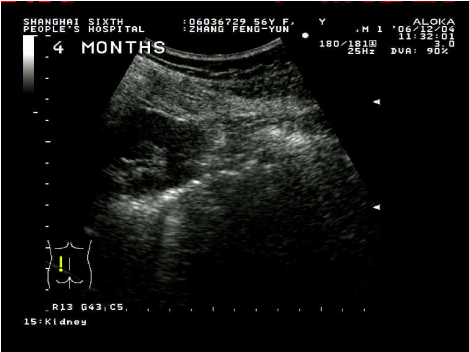

超聲引導下腎囊腫穿刺硬化治療具有簡單易行,患者少痛苦,復發率低,費用低等優點。這種方法是用超聲診斷儀事先選定穿刺點,設計好進針角度和進針深度,在局部麻醉下,用專用的穿刺探頭,根據已設定的角度和深度把直徑0.8毫米或1.2毫米的針插入囊腫,因為囊腫、針道和周圍臟器全部在超聲屏幕上看到,所以不會損傷周圍臟器,待抽凈囊液后,注入硬化劑,使硬化劑與囊腫內壁上皮接觸,達到硬化效果,數分鐘后把硬化劑抽出,拔出穿刺針,整個治療過程安全。在硬化治療后的早期(一個月內),一般說,囊腫上皮因硬化劑燒灼作用,會有滲出,一個月后開始漸漸吸收,三個月后明顯縮小,直至囊腫完全消失。

術后4月囊腫完全消失